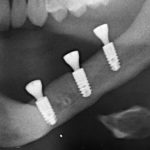

- компьютерная томография, поскольку это единственный способ объективно оценить биотип и измерить линейные параметры участка челюстной кости: